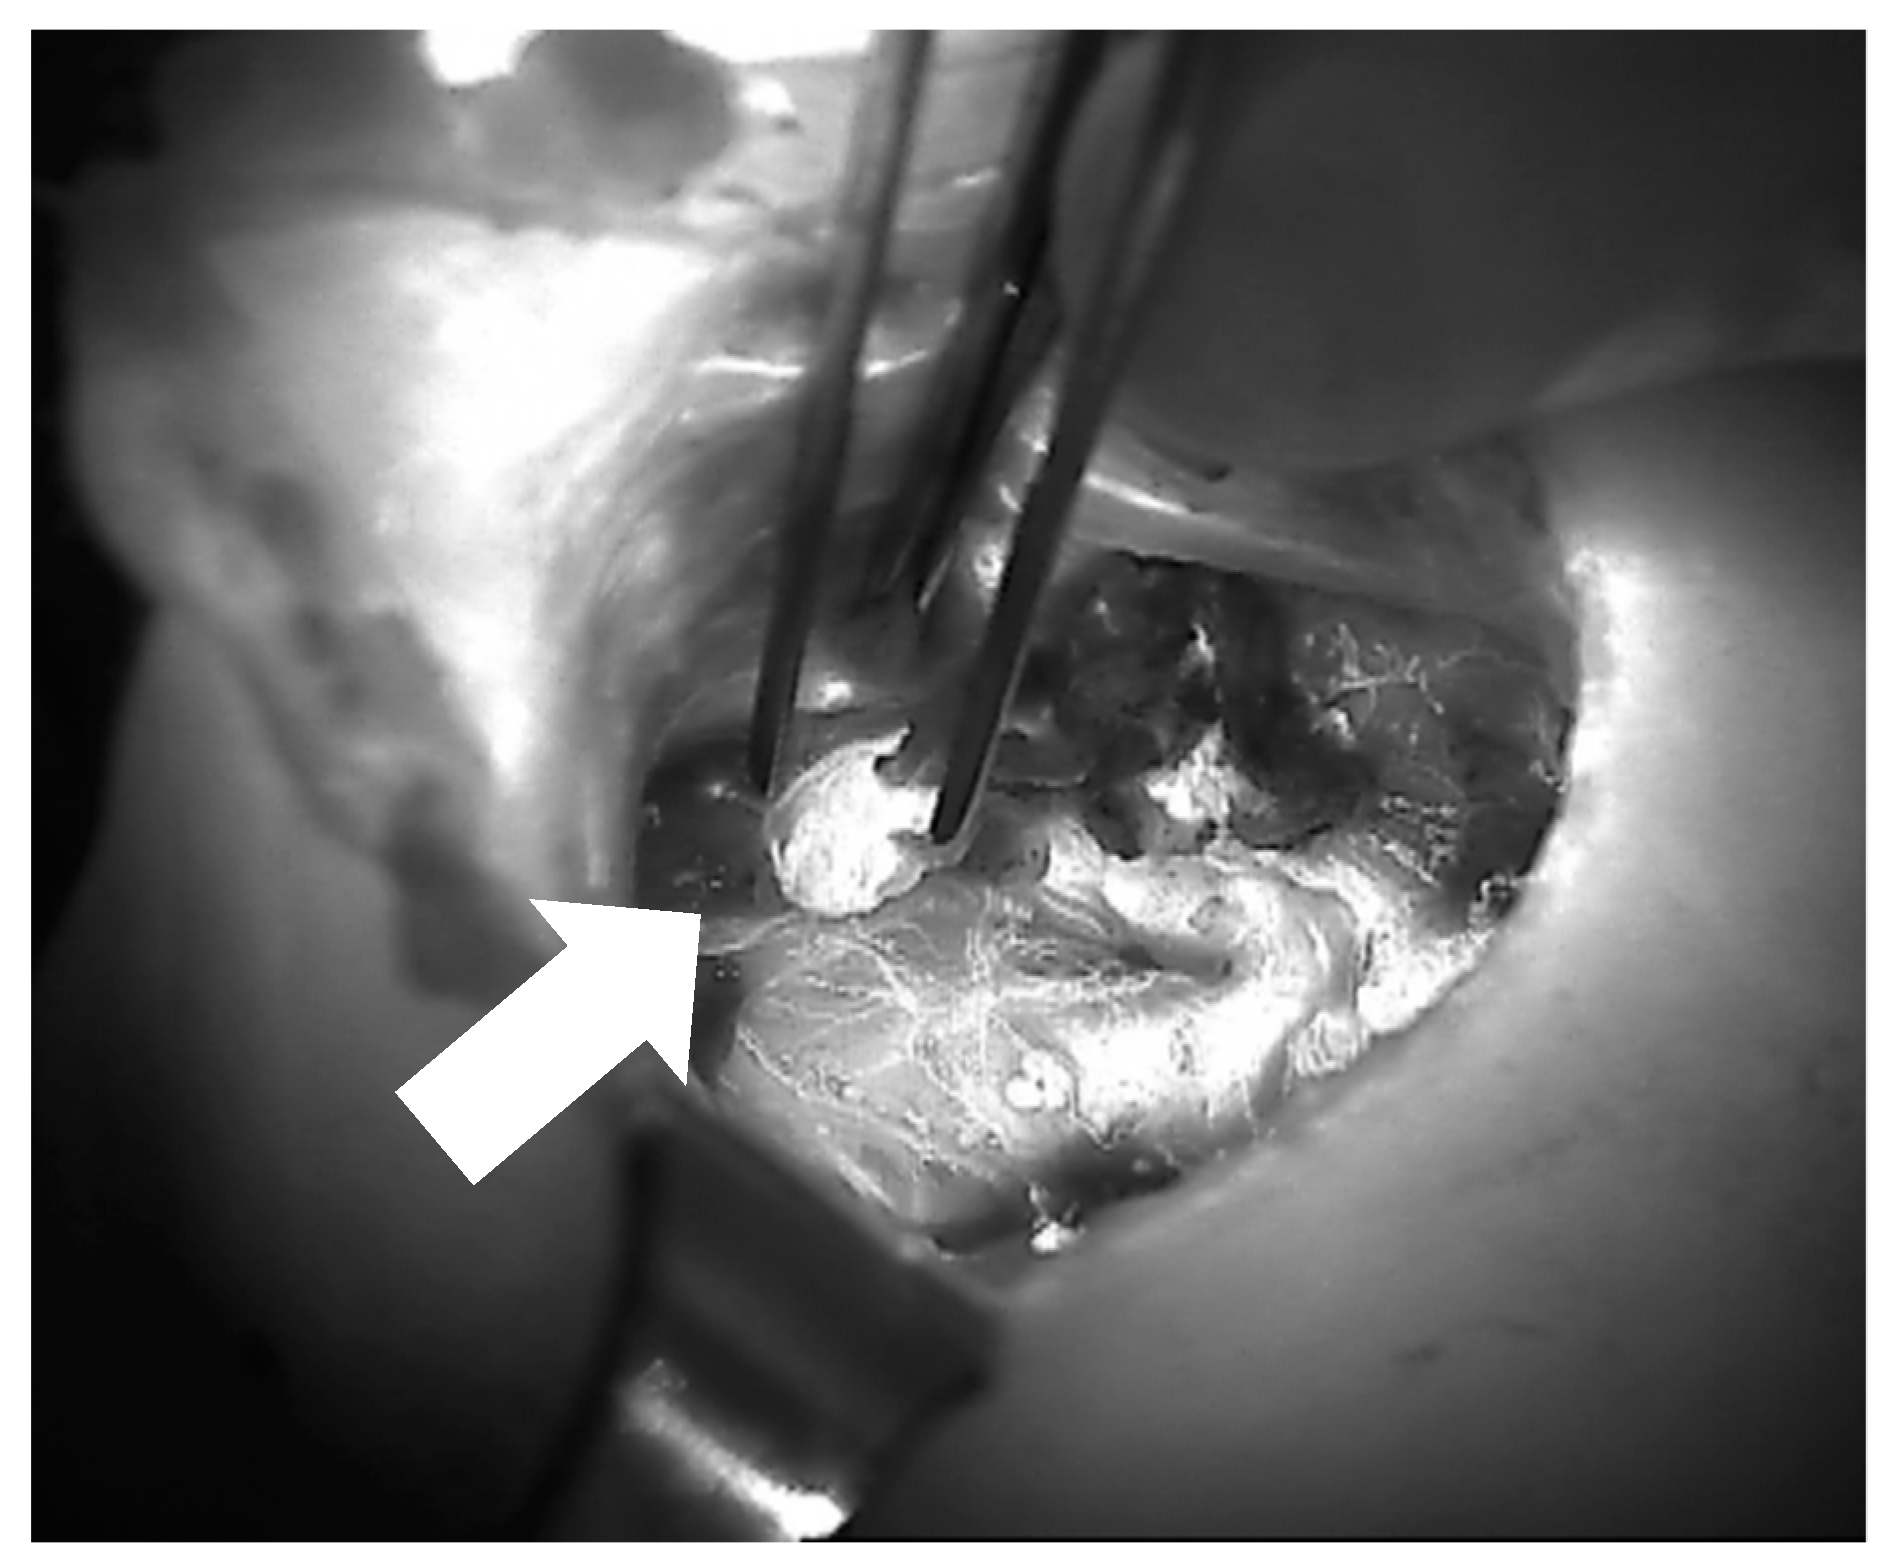

- Vidal Fortuny, J.; Belfontali, V.; Sadowski, S.M.; Karenovics, W.; Guigard, S.; Triponez, F. Parathyroid gland angiography with indocyanine green fluorescence to predict parathyroid function after thyroid surgery. Br. J. Surg. 2016, 103, 537–543. [Google Scholar] [CrossRef] [PubMed]

- Vidal Fortuny, J.; Sadowski, S.M.; Belfontali, V.; Guigard, S.; Poncet, A.; Ris, F.; Karenovics, W.; Triponez, F. Randomized clinical trial of intraoperative parathyroid gland angiography with indocyanine green fluorescence predicting parathyroid function after thyroid surgery. Br. J. Surg. 2018, 105, 350–357. [Google Scholar] [CrossRef] [PubMed]

- Rudin, A.V.; McKenzie, T.J.; Thompson, G.B.; Farley, D.R.; Lyden, M.L. Evaluation of Parathyroid Glands with Indocyanine Green Fluorescence Angiography After Thyroidectomy. World J. Surg. 2019, 43, 1538–1543. [Google Scholar] [CrossRef] [PubMed]

- Triponez, F. Re: Evaluation of Parathyroid Glands with Indocyanine Green Fluorescence Angiography After Thyroidectomy. World J. Surg. 2019, 43, 1544–1545. [Google Scholar] [CrossRef]

- Sadowski, S.M.; Fortuny, J.V.; Triponez, F. A reappraisal of vascular anatomy of the parathyroid gland based on fluorescence techniques. Gland Surg. 2017, 6, S30–S37. [Google Scholar] [CrossRef]

- Lang, B.H.-H.; Wong, C.K.H.; Hung, H.T.; Wong, K.P.; Mak, K.L.; Au, K.B. Indocyanine green fluorescence angiography for quantitative evaluation of in situ parathyroid gland perfusion and function after total thyroidectomy. Surgery 2017, 161, 87–95. [Google Scholar] [CrossRef]

- Razavi, A.C.; Ibraheem, K.; Haddad, A.; Saparova, L.; Shalaby, H.; Abdelgawad, M.; Kandil, E. Efficacy of indocyanine green fluorescence in predicting parathyroid vascularization during thyroid surgery. Head Neck 2019, 41, 3276–3281. [Google Scholar] [CrossRef]

- Gálvez-Pastor, S.; Torregrosa, N.M.; Ríos, A.; Febrero, B.; González-Costea, R.; García-López, M.A.; Balsalobre, M.D.; Pastor-Pérez, P.; Moreno, P.; Vázquez-Rojas, J.L.; et al. Prediction of hypocalcemia after total thyroidectomy using indocyanine green angiography of parathyroid glands: A simple quantitative scoring system. Am. J. Surg. 2019, 218, 993–999. [Google Scholar] [CrossRef]

- Jin, H.; Dong, Q.; He, Z.; Fan, J.; Liao, K.; Cui, M. Research on indocyanine green angiography for predicting postoperative hypoparathyroidism. Clin. Endocrinol. 2019, 90, 487–493. [Google Scholar] [CrossRef]

- Alesina, P.F.; Meier, B.; Hinrichs, J.; Mohmand, W.; Walz, M.K. Enhanced visualization of parathyroid glands during video-assisted neck surgery. Langenbeck’s Arch. Surg. 2018, 403, 395–401. [Google Scholar] [CrossRef] [PubMed]